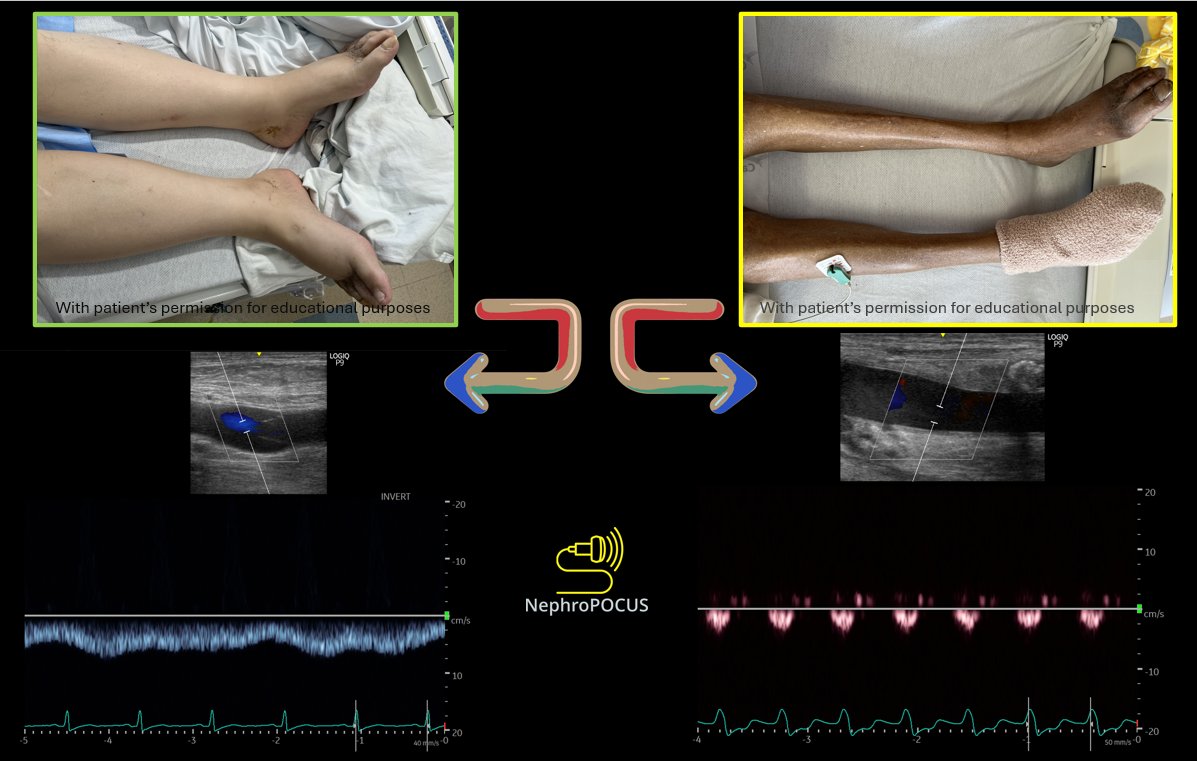

@NephroP

NephroPOCUS

4 days

One picture, enough said. This is why πŸ‘¨β€βš•οΈπŸ‘©β€βš•οΈ "feelings" about congestion don’t cut it. #POCUS #Nephpearls #VExUS #FOAMed